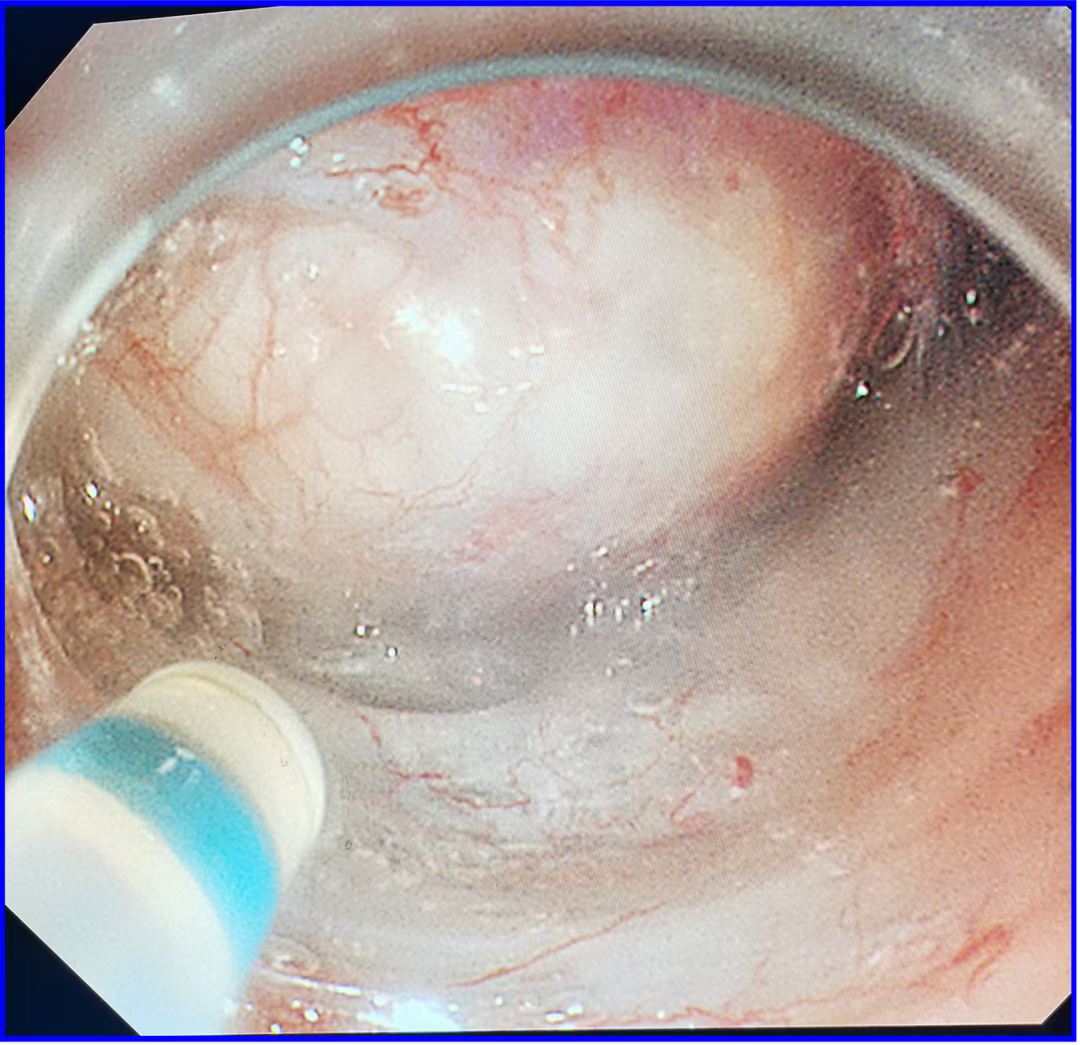

食管病灶

咽部病灶

1.(食管33处)食管糜烂型鳞状细胞癌,Ⅱ级,肿瘤大小0.6×0.3cm,癌组织局限于黏膜内(M2);淋巴管及血管内未见癌栓;送检组织四周及基底部切缘未见癌组织。免疫组化结果显示:CD34(未见癌栓),D2-40(未见癌栓),Desmin(平滑肌+),E-cadherin(+),Ki-67(index≈40%),P53(+,突变型)。

2.(下咽部)隆起型鳞状细胞癌,Ⅱ级,肿瘤大小1.8x1.2,癌组织侵及黏膜固有层;淋巴管及血管内未见癌栓;切缘及基底部切缘未见癌组织,(肿物距基底部切缘约200微米)。免疫组化结果显示:CD34(未见癌栓),C-erbB-2(1+),CK5/6(+),D2-40(未见癌栓),EGFR(+)、Ki-67(index≈50%),P53(-),P63(+)。

根据患者术后病检,患者达到临床治愈,无需放化疗,只需定期复查,真正做到了早发现、早治疗。